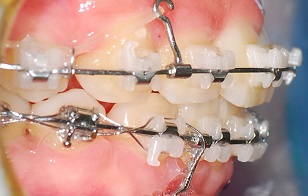

윗 니 발치공간이 다 닫힐 거라고 예상했던 것과 달리

아주 아주 조~금

0.5mm 정도 발치공간이 남았구

아래는 좀 더 많이 남았어요

계속 이렇게 고무줄로 공간을 줄이고

이 공간이 다 줄어들면

와이어를 교체한대요

처음 교정할 때 와이어가 점점 두꺼워졌다면

마지막 마무리 때는 와이어를 점점 얇은 것으로 교체하는 작업을 합니다.

그러면서 위아래 교합도 맞추고

환자가 원하는 치아 배열로 어느정도 맞추어요